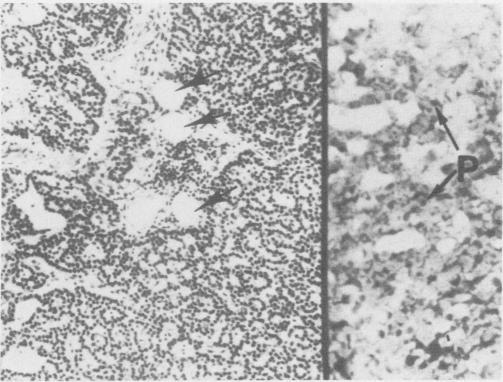

Normal and abnormal parathyroid glands removed surgically from 50 consecutive patients with primary hyperparathyroidism were studied by means of hematoxylin and eosin and oil-red-O stains. This was done to establish the incidence of the different pathological entities in our patient material, and to evaluate the role of the oil-red-O stain in the diagnostic histopathological process. The oil-red-O stain distinctly separates abnormally hyperfunctioning from normal or suppressed parathyroid tissue. Therefore, it is a valuable tool in the pathologic evaluation of patients with hyperparathyroidism. Chief cell adenomas were the most frequent lesions (88%), while diffuse hyperplasia was seen less commonly (10%) and carcinoma infrequently (2%). These findings justify a surgically conservative approach as the most desirable in managing patients with primary hyperparathyroidism.

对50例连续性原发性甲状旁腺功能亢进患者手术切除的正常及异常甲状旁腺进行苏木精-伊红染色和油红O染色研究。这样做是为了确定我们患者材料中不同病理实体的发生率,并评估油红O染色在诊断性组织病理学过程中的作用。油红O染色能清晰区分功能异常亢进的甲状旁腺组织与正常或受抑制的甲状旁腺组织。因此,它是甲状旁腺功能亢进患者病理评估中的一项有价值的工具。主细胞腺瘤是最常见的病变(88%),而弥漫性增生较少见(10%),癌罕见(2%)。这些发现证明手术保守 approach是治疗原发性甲状旁腺功能亢进患者最理想的方法。 (注:原文中“a surgically conservative approach”这里的“approach”直译为“方法”,结合语境可能更合适的表述是“手术方式”等,但按要求未添加解释,直接翻译为“方法”)